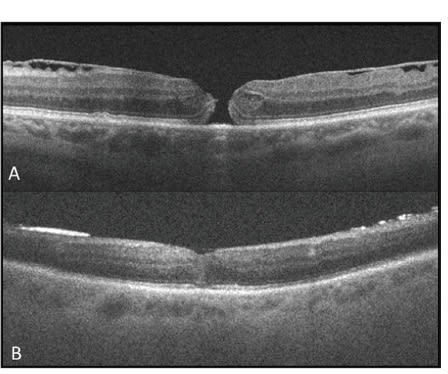

Figure 2. Intraoperative OCT scans during epiretinal membrane surgery. Preincision scan (A) reveals prominent ERM (red arrow) with inner retinal distortion. Postpeel scan (B) reveals residual membrane (orange arrow) and expansion of the IS/OS and cone outer segment tips to the RPE distance (red arrows). The outer retinal architectural changes are most prominent in the subfoveal area (yellow arrow).

Preliminary assessment suggested a significant expansion of the outer retinal hyporeflective band with an increased height in the inner segment/outer segment (ie, ellipsoid layer) to the RPE distance, as well as an increase in the cone outer segment tip (COST, ie, contact cylinder layer) to the RPE height (Figure 2, page 29).

Full-thickness architectural changes were also frequently seen at the initiation site of peeling. Functional analysis and postoperative OCT anatomic correlation are currently ongoing. Based on surgeon feedback forms, iOCT appears to identify undetected residual membranes in ~10% of cases that are subsequently peeled based on iOCT findings (Figure 2).